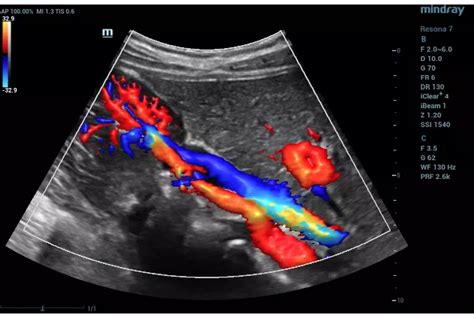

Color Doppler Imaging

Color Doppler imaging is a technique that allows visualization of blood flow within the body. It utilizes color coding to represent the direction and velocity of blood flow. By using color Doppler, you can assess the presence, direction, and characteristics of blood flow in various vessels or organs. This provides valuable information for diagnosing conditions such as vascular abnormalities, thrombosis, or the presence of tumors. Mastering the interpretation of color Doppler images can greatly enhance your ultrasound reading skills.